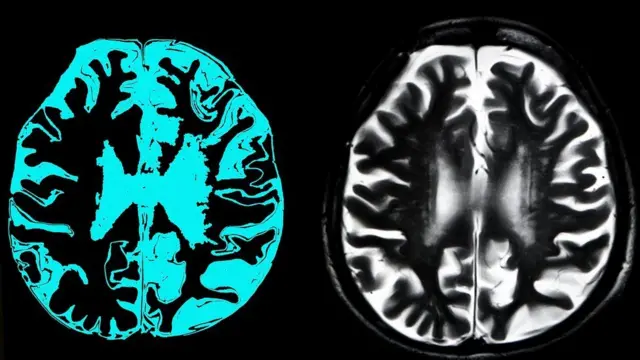

موت کے چار گھنٹوں بعد سور کا دماغ جزوی طور پر زندہ

زندگی اور موت کے درمیان کی لکیریں 2019 میں دھندلا گئیں۔

سور کو ذبح کرنے کے چار گھنٹے بعد اس کے دماغ کو جزوی طور پر زندہ کیا گیا۔

تحقیق کے مطابق اعصابی خلیوں کی موت کو روکا جا سکتا ہے اور دماغ کی کچھ تاروں کو بحال کیا جا سکتا ہے۔

ایسا مصنوعی خون کو دھڑ سے الگ ہوئے دماغ میں پہنچا کر کیا گیا۔

یہ تحقیق اس آئیڈیا کو چیلنج کرتی ہے کہ خون کی سپلائی دماغ تک نہ پہنچنے سے نا قابلِ تلافی نقصان ہو جاتا ہے اور یہ ذہنی امراض کے لیے نئے علاج کا سبب بن سکے گی۔

تاہم، دماغ سے ایسے کوئی سگنلز نہیں ملے جس سے دماغ کے ہوش میں ہونے کا ثبوت ملے۔